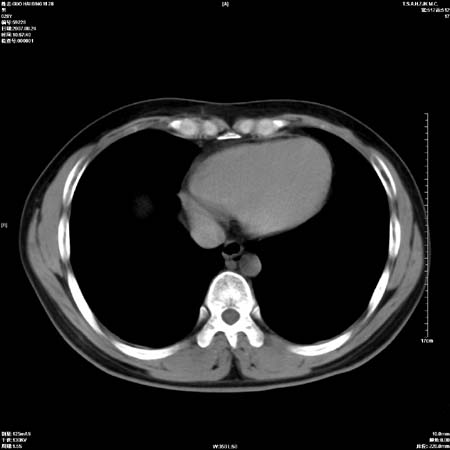

肺癌并纵隔淋巴结转移。

左肺中心型肺癌并纵隔淋巴结转移!考虑为小细胞肺癌,没有手术机会了,只能进行放化了,疗效不错,但极易复发。没办法,现在肿瘤年轻化越来越明显了。

左上肺癌伴纵隔淋巴结转移.